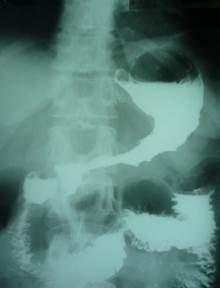

Женщина, 70 лет, 4 года назад перенесла инфаркт миокарда. При контрольном осмотре у кардиолога предъявила жалобы на чувство быстрого насыщения и ощущение полноты в желудке после приема небольших порций пищи. Других желудочных и общесоматических жалоб не предъявляла.

История заболевания. Указанные симптомы возникли без видимой причины 2 месяца назад. Никакой динамики за этот период не наблюдалось.

Врач направила больную на рентгенологическое обследование и ФГС.

2. Какое заключение должно быть сделано по рентгенограммам?